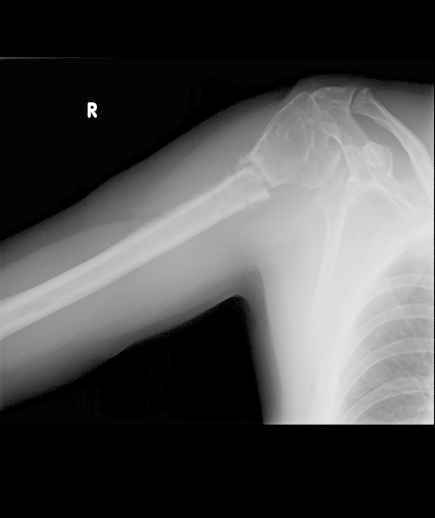

Na radiogramie uwidoczniono złamanie

A. wyrostka barkowego łopatki.

B. wyrostka kruczego.

C. dalszego końca kości ramiennej.

D. bliższego końca kości ramiennej.